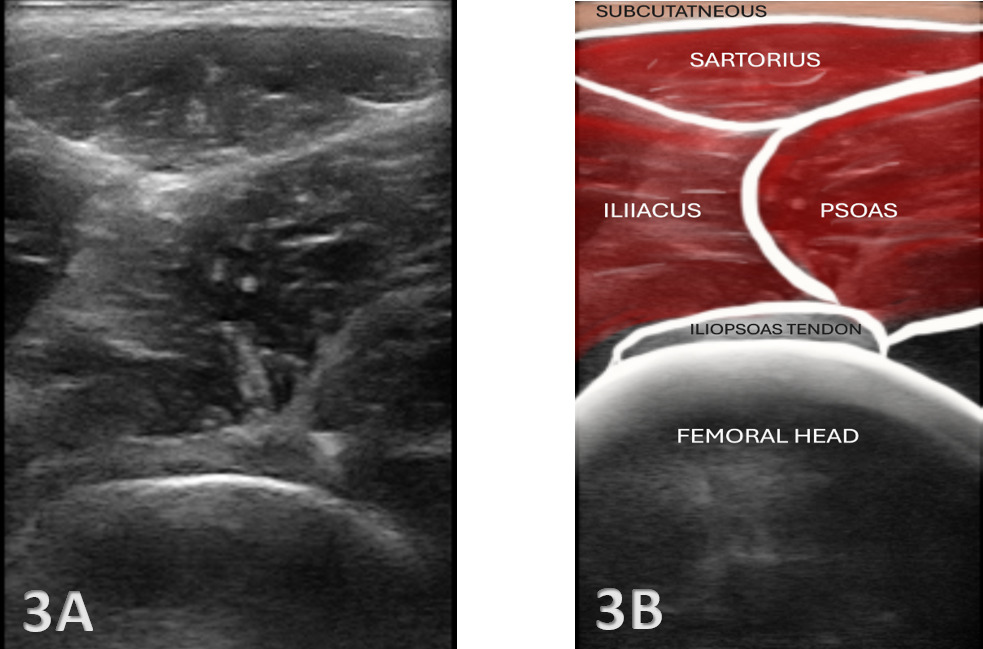

Proper patient positioning and transducer placement are crucial for visualizing the iliopsoas. The patient is typically positioned supine with the hip slightly externally rotated to improve access to the anterior hip region. A high-frequency linear transducer (7-12 MHz) is commonly used to visualize the iliopsoas complex. A curvilinear transducer may be necessary for deeper visualization.

Transverse Plane: The transducer is placed parallel to the inguinal ligament to identify the femoral vessels, then moved laterally to locate the iliopsoas muscle.

Normal Anatomy: The iliopsoas muscle appears as a hypoechoic (darker) striated structure with internal echogenic (brighter) fibrous septa typical of a muscle.12 The tendon is more echogenic and is best visualized near its insertion on the lesser trochanter.

Bursitis: Iliopsoas bursitis may present as an anechoic or hypoechoic fluid collection between the iliopsoas tendon and the hip joint capsule. The bursa originates at the level of the femoral head and typically extends medially and possibly deep to the psoas major tendon and iliopsoas tendon.13 An iliopsoas bursitis will present as hip and groin pain. Bursal distensions rarely produce compression neuropathy of the femoral nerve; however, large distensions may extend into the pelvis along the iliacus muscle and may displace the pelvis structures.14 Management includes anti-inflammatory strategies and ultrasound-guided bursal injections.